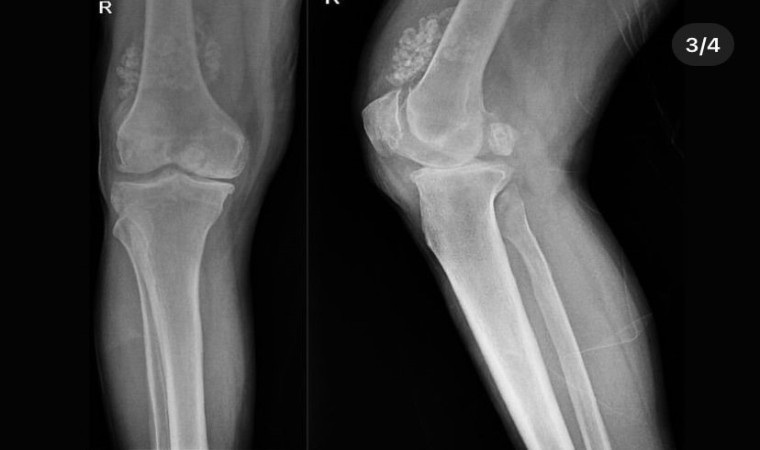

Diz ağrısı şikayeti ile geldiği Düzce Üniversitesi Tıp Fakültesi Hastanesi’nde ameliyata alınan hastanın dizlerinden toplam 41 adet multipl sinovial kondromatozisi çıkartıldı. Özellikle diz eklemi çevresinde görülmekle birlikte kalça, dirsek ve diğer eklemlerde de görülen, ufak parçalardan oluşan cisimler olarak tanımlanan eklem faresi, eklem çevresinde eklem sıvısı ya da sinoviyumda görülen kıkırdak ya da kemik parçalarıdır. Eklem farelerinin boyutları birkaç milimetreden birkaç santimetreye kadar çıkabiliyor.